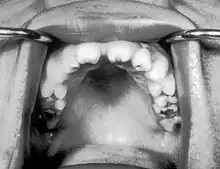

Notched incisors known as Hutchinson's teeth which are characteristic of congenital syphilis

• Blunted upper incisor teeth known as Hutchinson's teeth

A frequently-found group of symptoms is Hutchinson's triad, which consists of Hutchinson's teeth (notched incisors), keratitis and deafness and occurs in 63% of cases.[18]